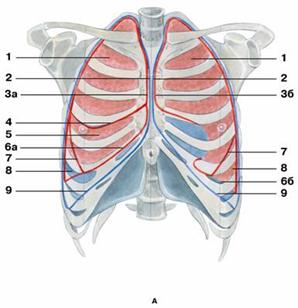

В клинической практике необходимо определять границы легких: переднюю, нижнюю и заднюю. Верхушки легких выступают выше ключицы на 2-3 см. Передняя граница (проекция переднего края) спускается от верхушек обоих легких по грудине, проходит почти параллельно на расстоянии 1-1.5 см до уровня хряща IV ребра. Здесь граница левого легкого отклоняется влево на 4-5 см, образуя сердечную вырезку. На уровне хряща VI ребра передние границы легких переходят в нижние. Нижняя граница легких соответствует по среднеключичной линии VI ребру, по средней подмышечной линии -VIII ребру, по лопаточной - X ребру, по околопозвоночной - XI ребру. Нижняя граница левого легкого расположена на 1-2 см ниже приведенной границы правого легкого. При максимальном вдохе нижний край легкого спускается на 5-6 см. Задняя граница легких проходит по околопозвоночной линии (по головкам ребер).

Рис. Границы легких

Рис. Границы легких

А — вид спереди:

1 — верхняя доля легкого;

2 — передняя граница плевры

3 — передний край легкого: а) правого; б) левого;

4 — горизонтальная щель;

5 — средняя доля;

6 — нижний край легкого: а) правого; б) левого;

7 — косая щель;

8 — нижняя доля;

9 — нижняя граница плевры;

Рис. Границы легких